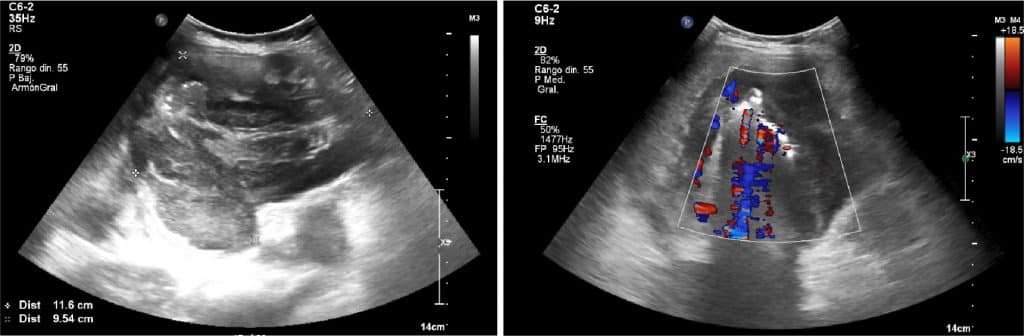

ECOGRAFÍA ABDOMINAL

En la ecografía abdominal, se observa una masa intraperitoneal de aprox. 10 cm de diámetro máximo localizado en el hemiabdomen derecho, de aspecto heterogéneo y con flujo al Doppler color.